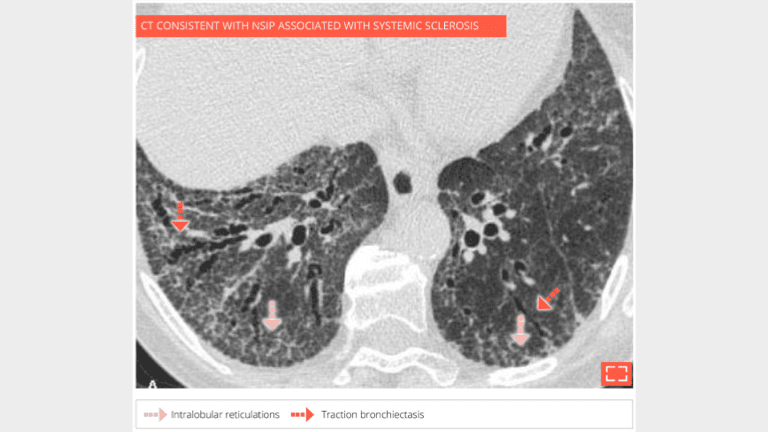

3. Intralobular reticulations

• Isolated and subtle subpleural intralobular reticulations and traction bronchiectasis of the 2 lower lobes.

• No ground-glass opacity or honeycombing.